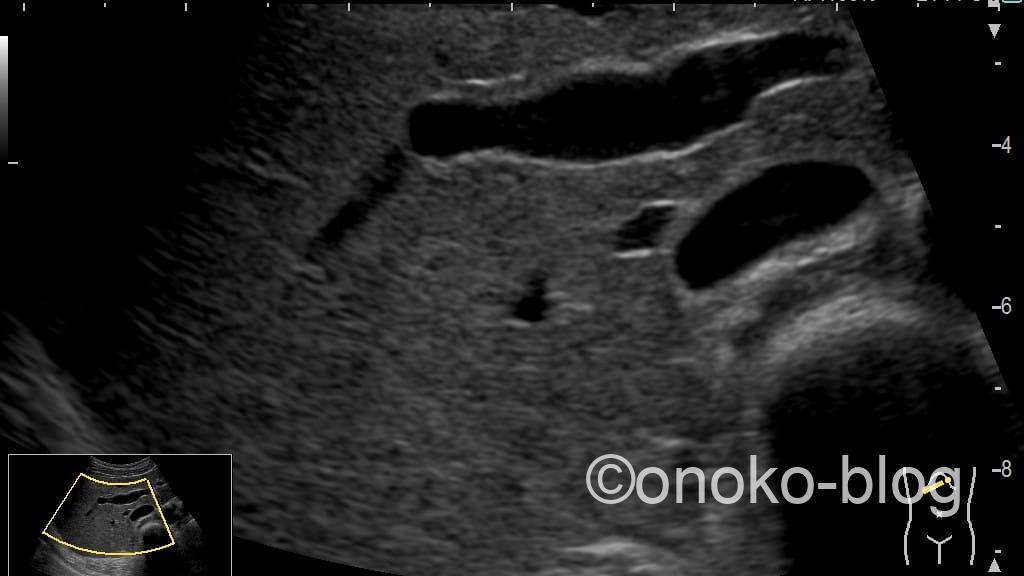

次はWrite Zoomで記録した画像です。

おお、走査線数が増えているから全くぼやけないですね。